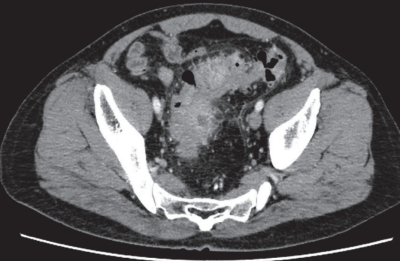

尿所見:蛋白(-)、糖(-)、潜血(-)。血液所見:赤血球 468 万、Hb 13.9 g/dL、Ht 42 %、白血球 12,300(桿状核好中球 30 %、 分葉核好中球45 %)、血小板 20 万。血液生化学所見:総蛋白 7.5 g/dL、アルブミン 3.9 g/dL、総ビリルビン 0.9 mg/dL、AST 28 U/L、ALT 16 U/L、LD 177 U/L(基準 120~245)、ALP 83 U/L(基準 38~113)、γ-GT 48 U/L(基準 8 ~50)、アミラーゼ 95 U/L(基準 37~160)、尿素窒素 12 mg/dL、クレアチニン 0.6 mg/dL、血糖98 mg/dL。CRP 3.2 mg/dL。 1 年前に行われた下部消化管内視鏡検査の S 状結腸像と今回来院時の腹部造影 CTを別に示す。